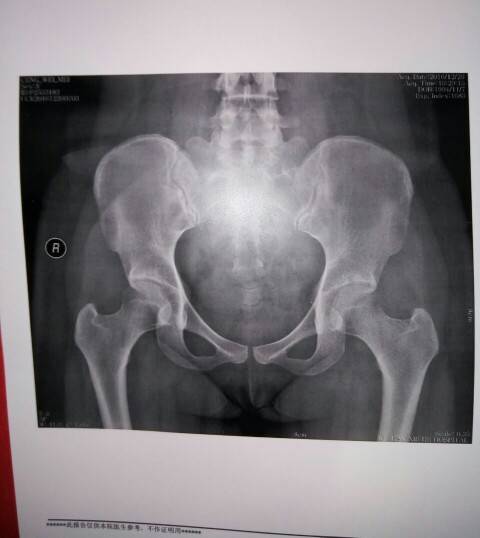

出现股骨头骨质疏松就是股骨坏死,这是刚开始。注意不要负重行走,每天及时补充足量的钙和维生素D,最好能够每天睡前泡脚半小时

骨密度不均匀,最好能核磁共振再看看,核磁更准确些